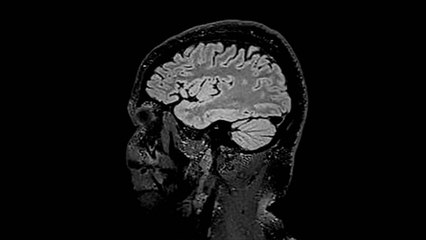

Afectación cerebral, otro daño colateral en pacientes Covid-19

La neumonía es una de las principales complicaciones del COVID-19 pero, aunque es considerada una afección respiratoria, el SARS-CoV-2 también tiene otras complicaciones asociadas como al afectación cerebral.